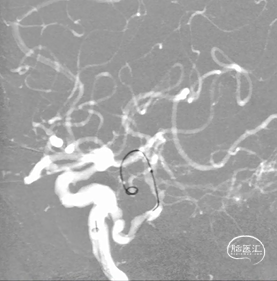

3. L-ICA(三维重建):(图3)

图3

2. 3D重建:L-P2段动脉瘤,瘤体:3.9mm*4.5mm,瘤颈:3.9mm。L-PCA-P2段瘤体近端局限性狭窄,狭窄率约60%,左侧颈内动脉C6段小动脉瘤:1mm*1.5mm,瘤体向下。(图8)

图8